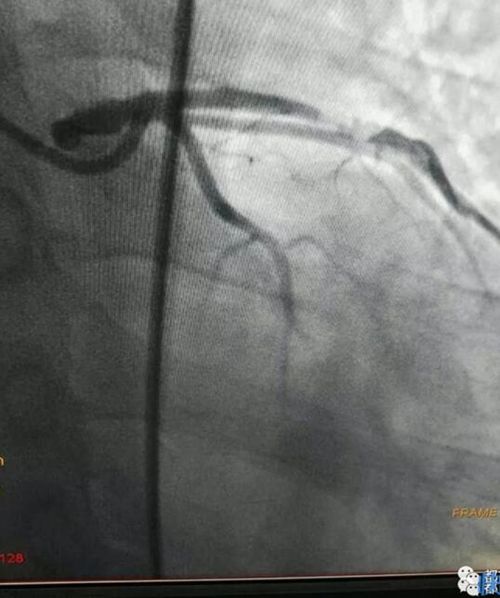

梁毅、葉興、戴瑞醫(yī)生和導(dǎo)管室的護(hù)士、技師們密切協(xié)作,以最快的速度完成經(jīng)右股動(dòng)脈的冠狀動(dòng)脈造影,發(fā)現(xiàn)有一塊血栓堵在了李先生冠狀動(dòng)脈前降支近段的血管上,同時(shí)發(fā)現(xiàn)這段血管99%狹窄,立即予以植入支架并及時(shí)抽吸及局部藥物注入,恢復(fù)了前向血流,有效終止了電風(fēng)暴的發(fā)作。

栓塞的血管造影